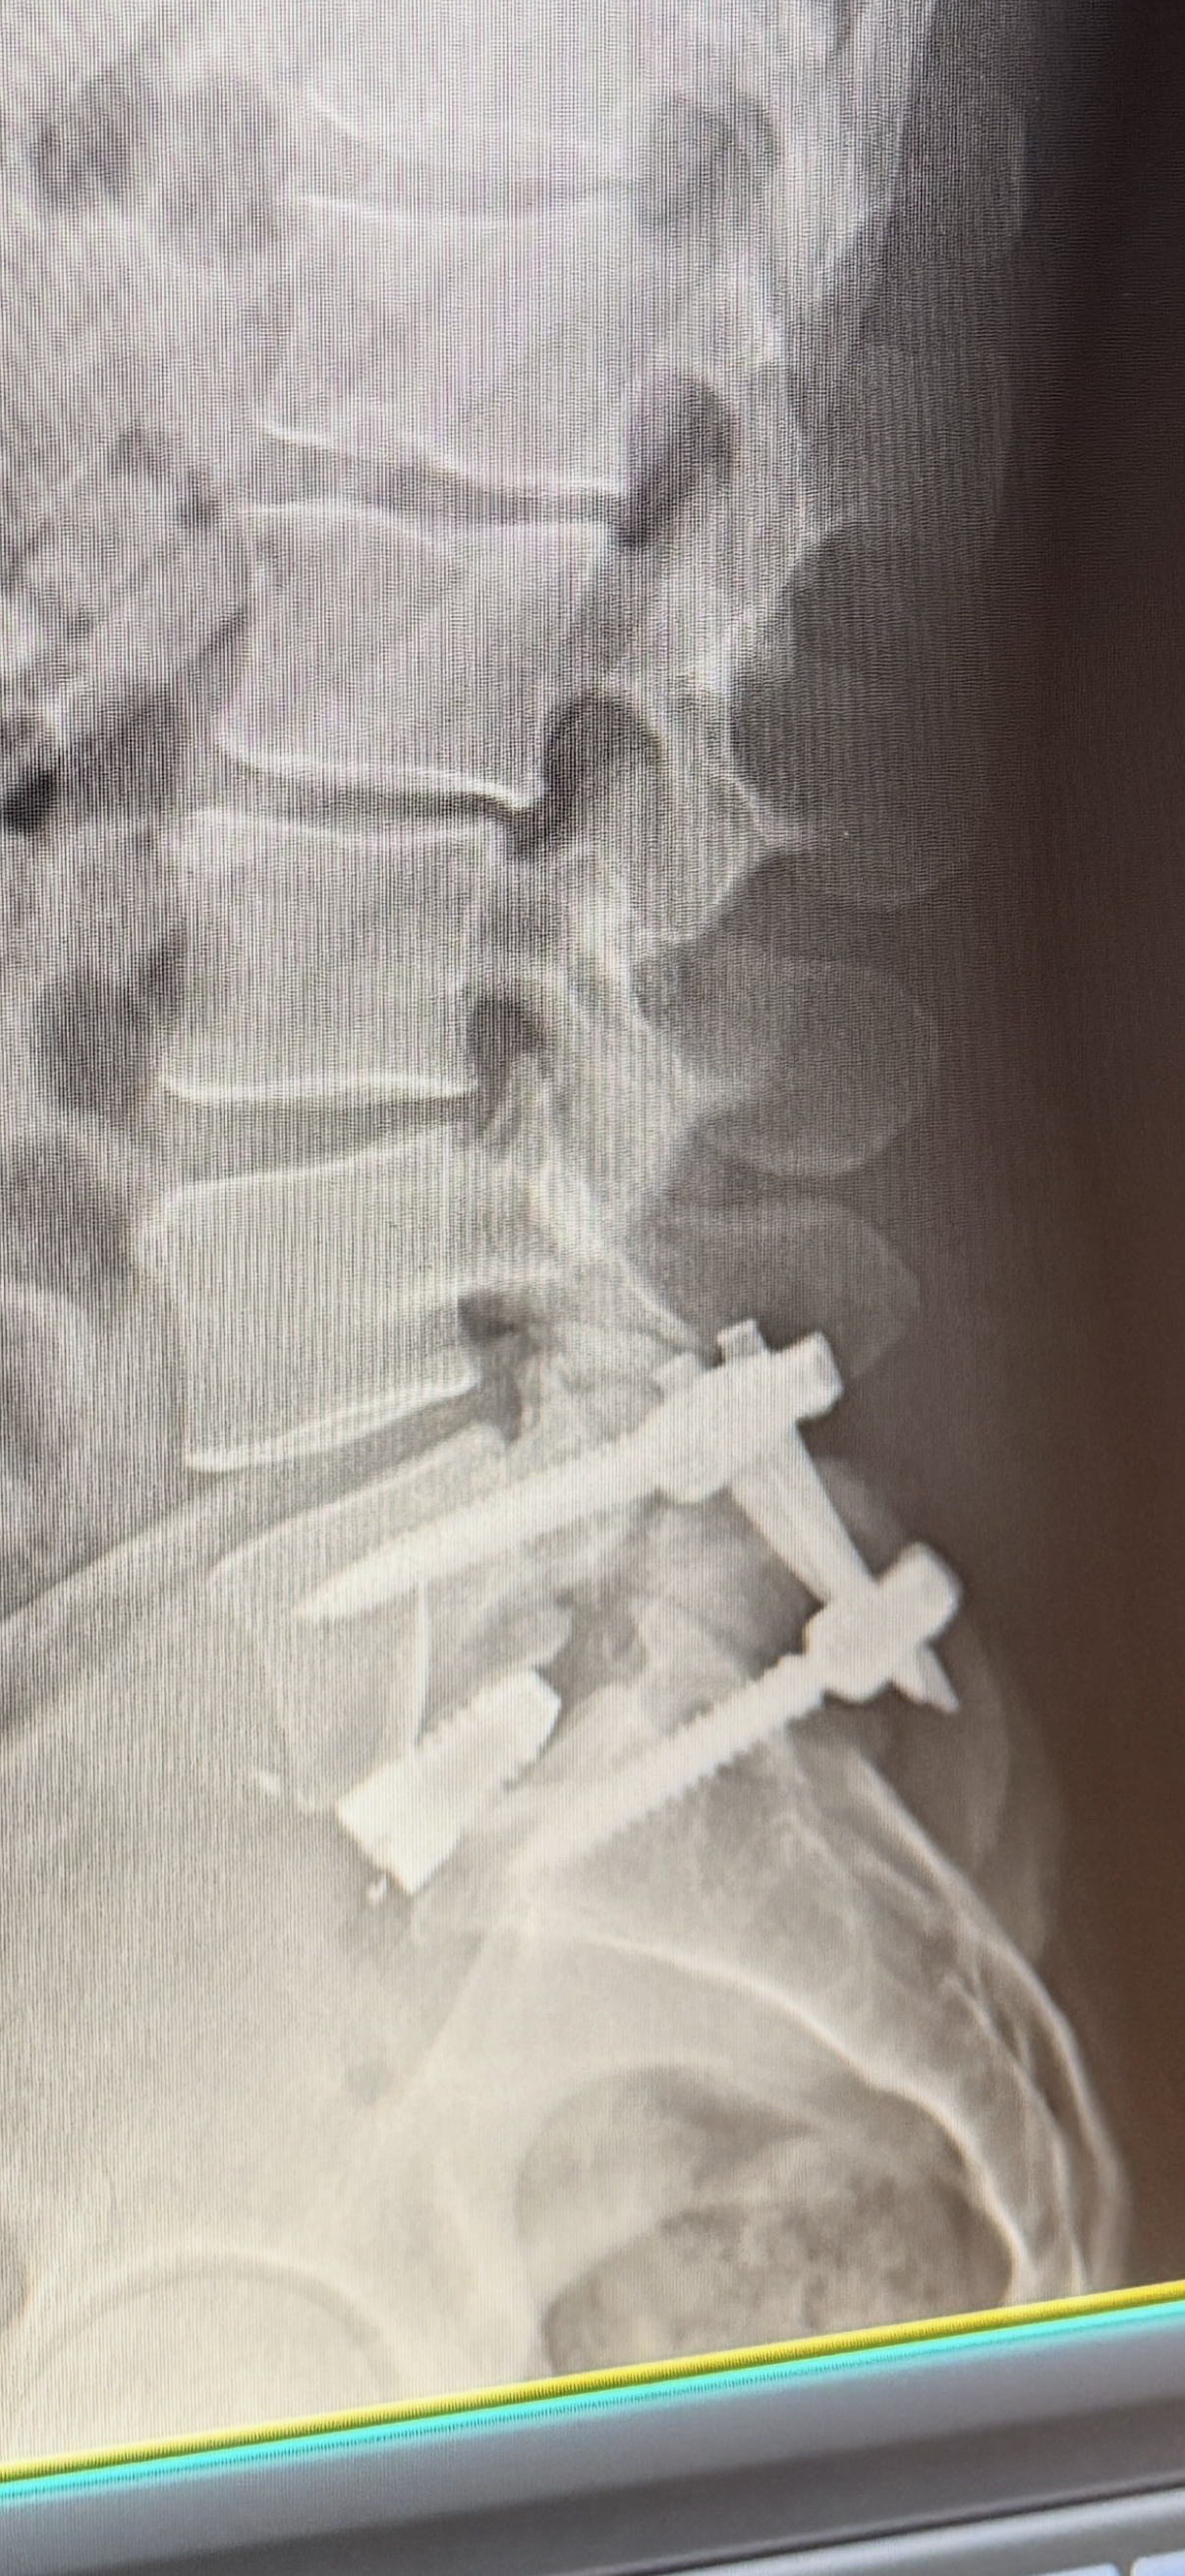

Paul needed an emergency L5-S1 anterior/posterior fusion of his spine for a traumatic injury he sustained as a teenager. After living nearly 2 decades with chronic problems from the fracture in his L5-S1, the remaining structure finally failed and began impinging on nerves which required immediate intervention. Any donation to support Paul financially during this time is greatly appreciated. Unfortunately this was not due to a climbing incident so it will not be covered under L&I or Worker’s Comp. Paul has exhausted his paid time off leave bank with his Firefighter/Paramedic job, and subsequently his entire recovery will largely be unpaid.